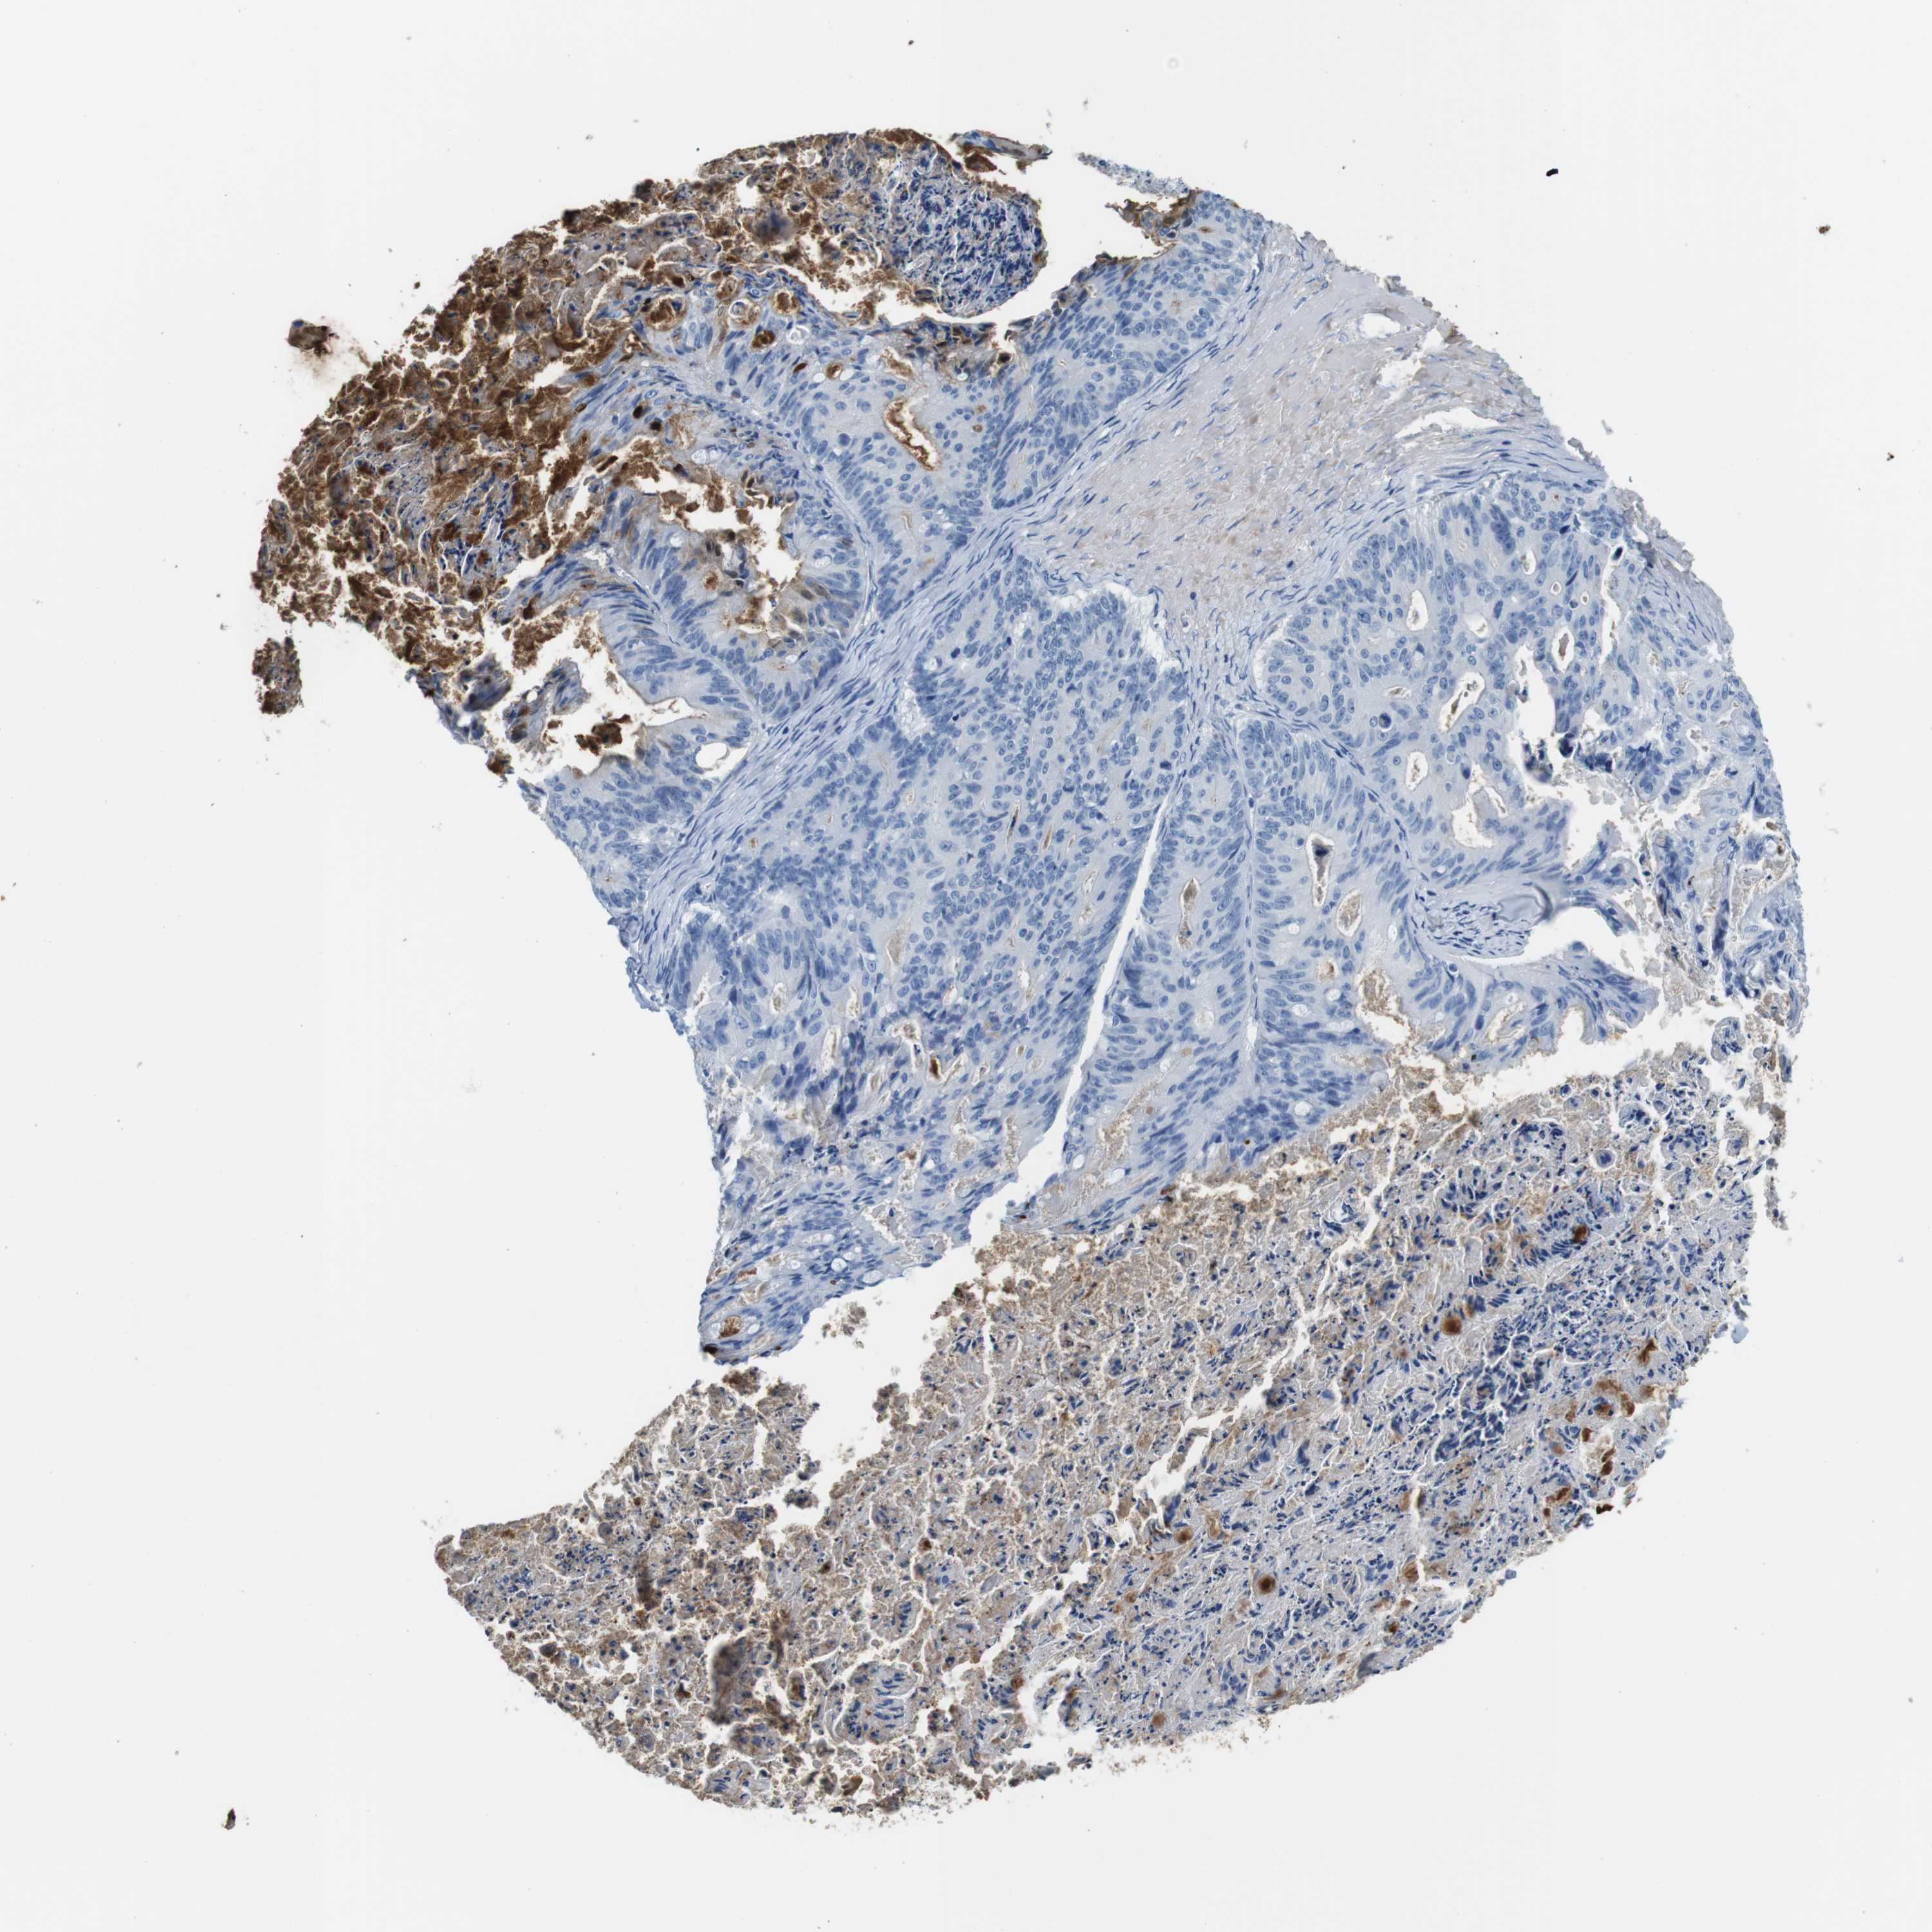

OVARIAN CANCER - Protein expressioni

A mouse-over function shows sample information and annotation data. Click on an image to view it in a full screen mode. Samples can be filtered based on level of antibody staining by selecting one or several of the following categories: high, medium, low and not detected. The assay and annotation is described here.

Note that samples used for immunohistochemistry by the Human Protein Atlas do not correspond to samples in the TCGA dataset.

Antibody stainingi

Antibody staining in the annotated cell types in the current human tissue is reported as not detected, low, medium, or high, based on conventional immunohistochemistry profiling in selected tissues. This score is based on the combination of the staining intensity and fraction of stained cells.

Each image is clickable and will lead to virtual microscopy that enables deeper exploration of all samples and also displays staining intensity scores, fraction scores and subcellular localization as well as patient and tissue information for each sample.

Antibody CAB015377

Staining

High

Medium

Low

Not detected

Intensity

Strong

Moderate

Weak

Negative

Quantity

>75%

75%-25%

<25%

None

Location

Nuclear

Cytoplasmic/membranous

Cytoplasmic/membranous,nuclear

Cystadenocarcinoma, serous, NOS

Carcinoma, endometroid

Cystadenocarcinoma, mucinous, NOS

Carcinoma, NOS